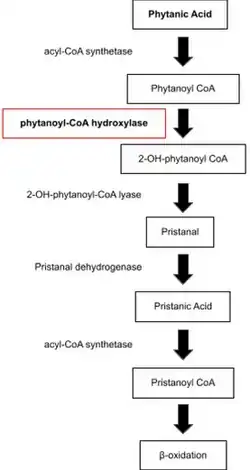

Refsum disease is a peroxisomal disorder caused by the impaired alpha-oxidation of branched chain fatty acids resulting in buildup of phytanic acid and its derivatives in the plasma and tissues. This may be due to deficiencies of phytanoyl-CoA hydroxylase or peroxin-7 activity. In general, Refsum disease is caused by PHYH mutations.[1][14]

Adult Refsum disease may be divided into the adult Refsum disease 1 and adult Refsum disease 2 subtypes. The former stems from mutations in the phytanoyl-CoA hydroxylase (PAHX aka PHYH) gene, on the PHYH locus at 10p13 on chromosome 6q22-24.[15] It was initially believed this was the sole mutation; however 55% of cases are now attributed to mutations in other genes.[17]